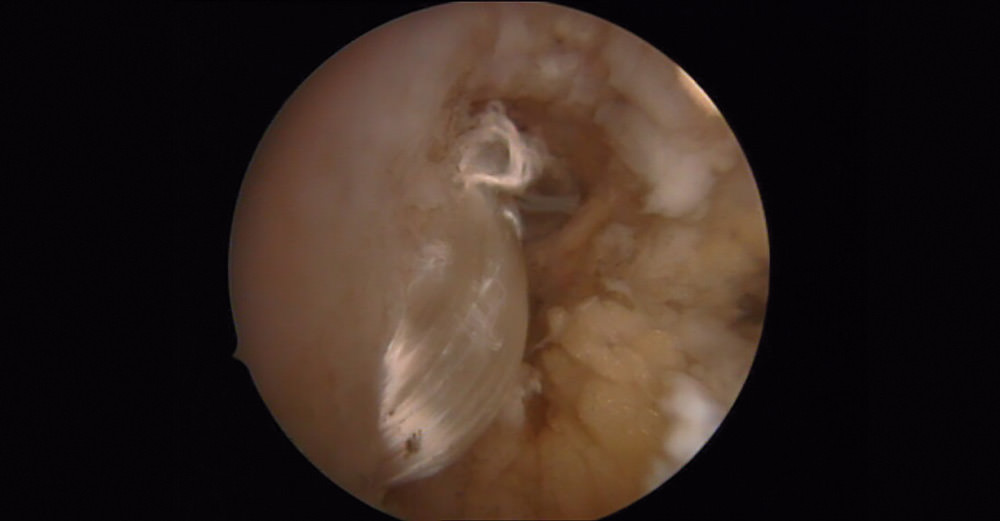

Una vez tratadas el resto de las patologías, con la cámara en el portal anteromedial y los instrumentos por el anterolateral, realizamos una limpieza con motor y vaporizador de todas las adhesiones, sinovitis... que podemos encontrar en el receso lateral y las cuales nos podrían dificultar la manipulación de la plastia.

Una vez colocados los 2 tornillos, se puede objetivar la estabilidad de la plastia intraarticularmente con el artroscopio y externamente con un gentil movimiento varo-valgo (Figura 8).

Figura 8. Plastia una vez realizado el bloqueo a nivel del astrágalo. Resultado final.

En las artroscopias, en todos los casos se observó una rotura completa del LPAA con presencia de fibras del ligamento en diferentes fases degenerativas.